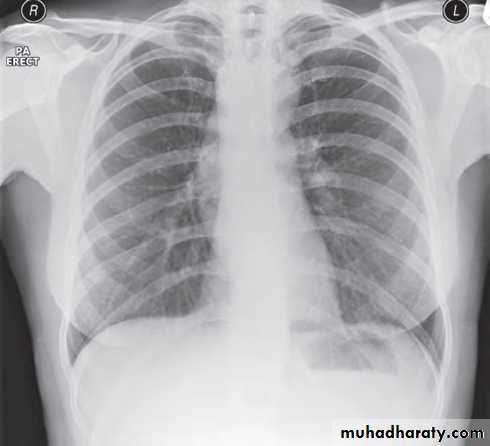

Standard views are the PA & Lateral

PA ( frontal ) VIEW LT. LATERAL VIEW

1) CXR

Parts :• 1) Lungs ( Both lung fields )

• 2) Mediastinum

• 3) Chest wall (ribs& soft tissues )

• 4) Diaphragm

• 5) HilaGood CXR = correct diagnosis